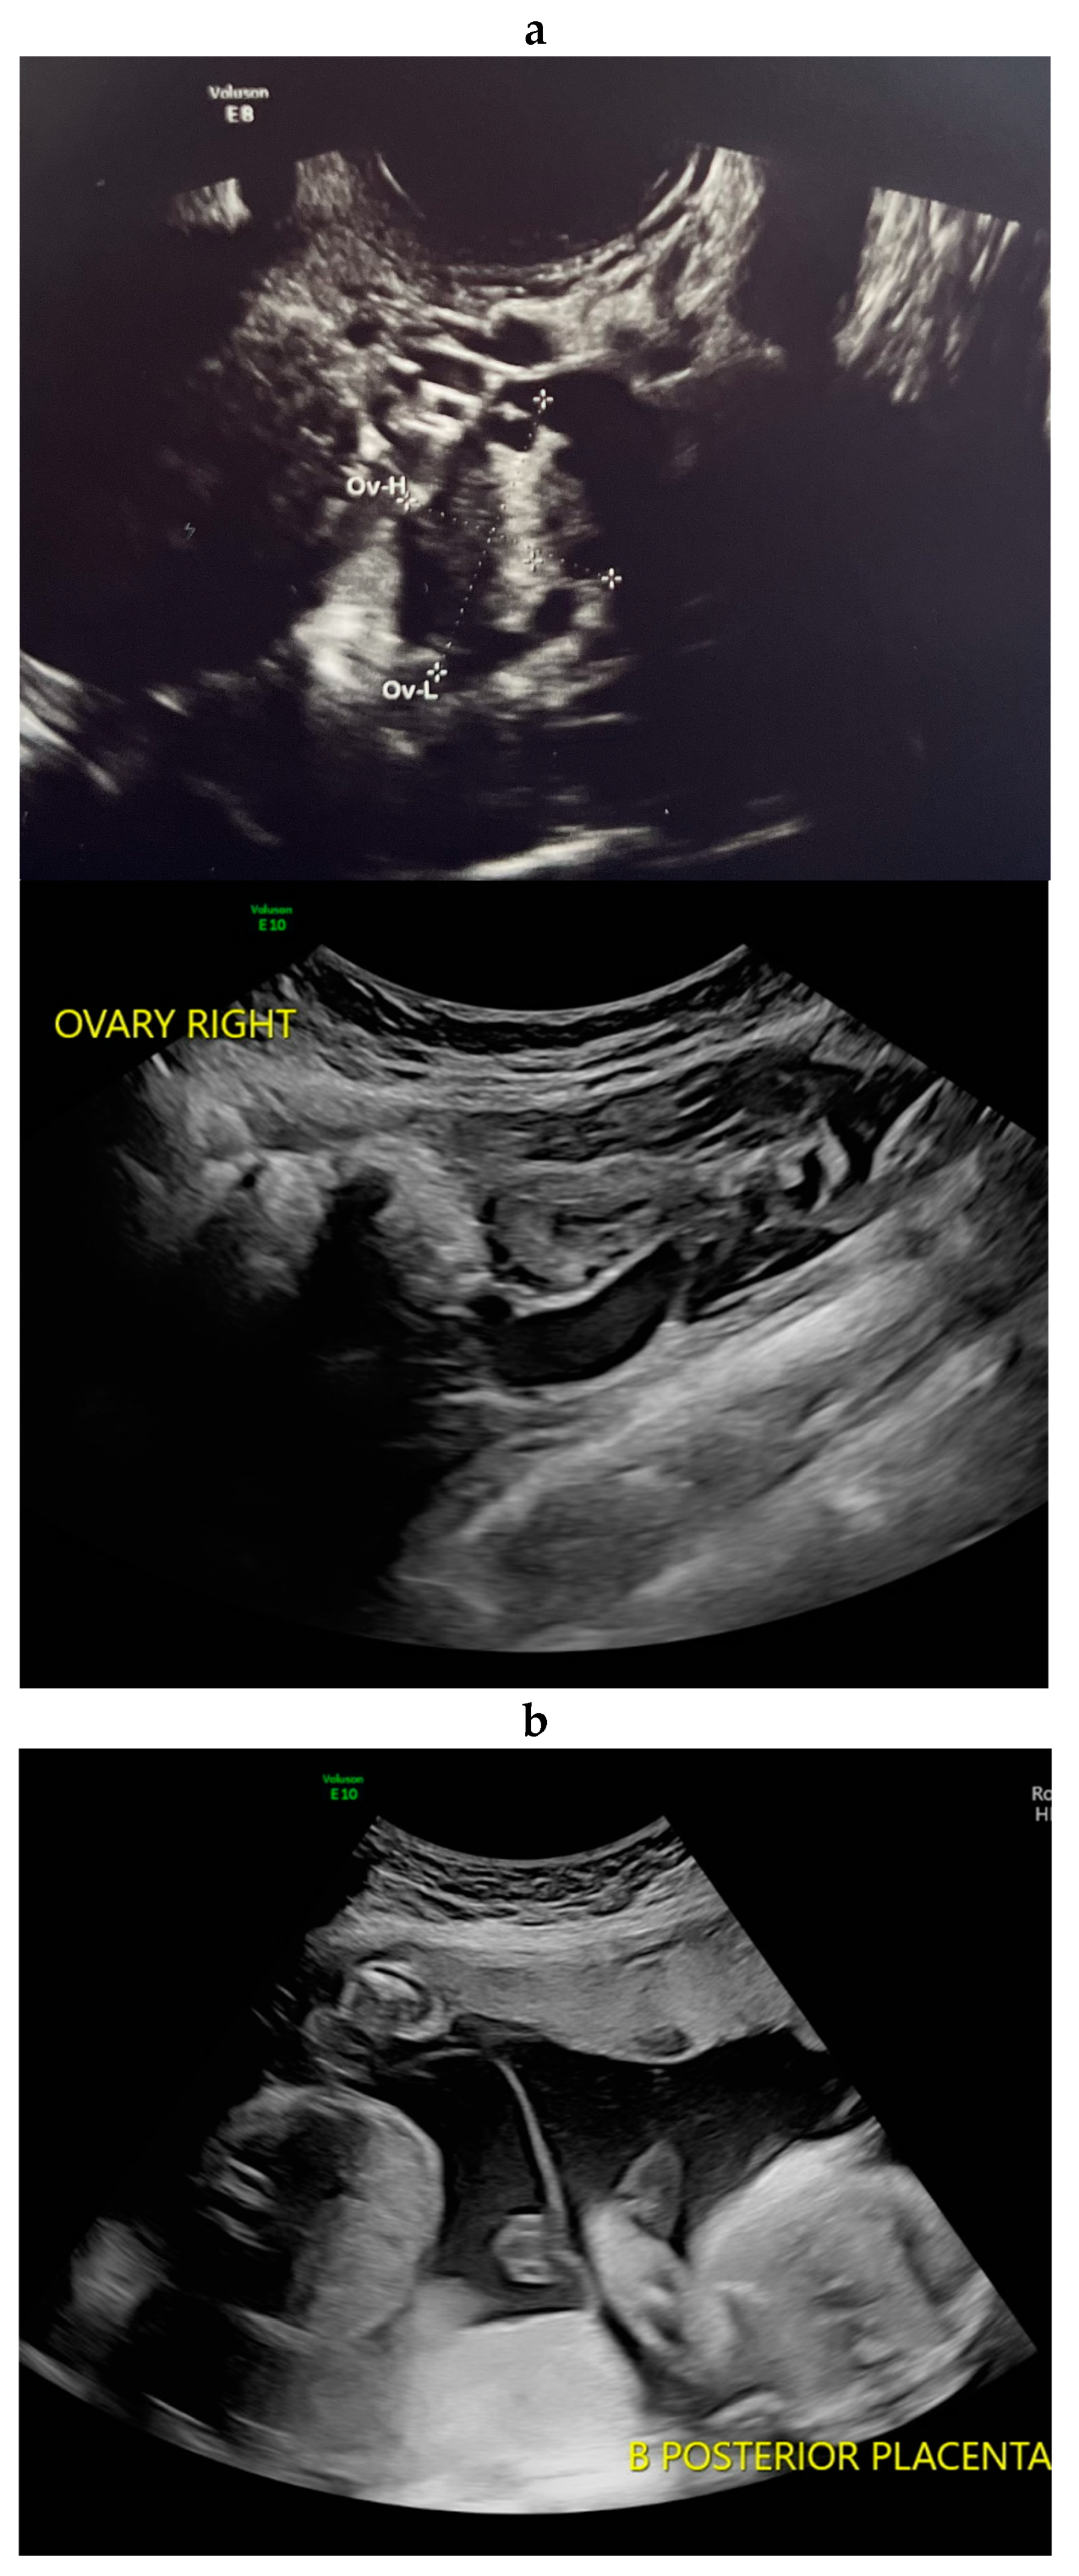

2. Case Presentation